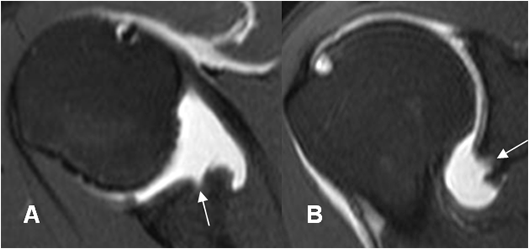

Fig 50 B. Bankart óseo.

A: ArtroRM axial en STIR y B: ArtroRM sagital en STIR. Defecto del reborde anterior inferior de la glenoides y el labrum articular, por lesión de Bankart óseo. (Flechas).